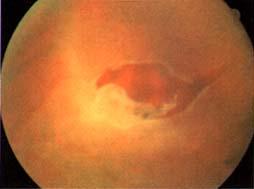

その日は安静にして翌朝一番に病院へ行ったところ、「ベッドに空きがないけど何とかするから今日手術しましょう。」ということになった。大ごとである。何でも網膜に穴が開いて破れ、水が染み込んで壁紙が浮いたように剥がれたらしい。ちょっとでも手遅れになると失明確実いう病気らしい。自分ひとりなら高を括って先延ばしにしていたところだ。女房殿に感謝である。

いやはや教科書に載せたいくらい、お見事な網膜裂孔の眼底所見です。

「盲点は網膜にあり」は、迷言!?ですが、飛蚊症に視野欠損こそが網膜の

悲痛な叫び!数日遅かったら失明でしたよ。本当に奥様に感謝しないと。

網膜復位術を行ったのだと思いますが、術後の経過は順調と言っても、

決して油断は禁物。違和感があれば、即眼科直行ですよ〜。